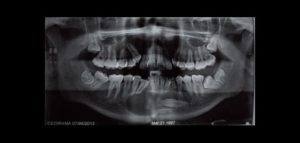

Las imágenes obtenidas mediante CBCT han asumido un papel prominente en el diagnóstico de la disfunción de la articulación temporomandibular (ATM), para la evaluación de